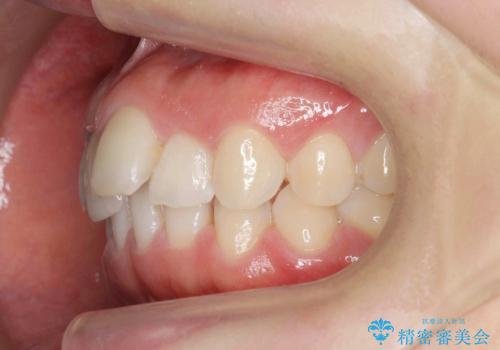

前歯のガタつきをきれいに マウスピース矯正治療

- 「前歯のガタつきをきれいにしたい。」と矯正治療を希望され来院されました。

前歯のガタつきをワイヤー部分矯正、上顎前突の咬合関係を後方移動することで理想的な咬合関係を確立します。

上顎の全体的な後方移動を実現するためにマイクロインプラントを併用したゴムかけを行ったことで理想的な咬合関係を確立することができました。